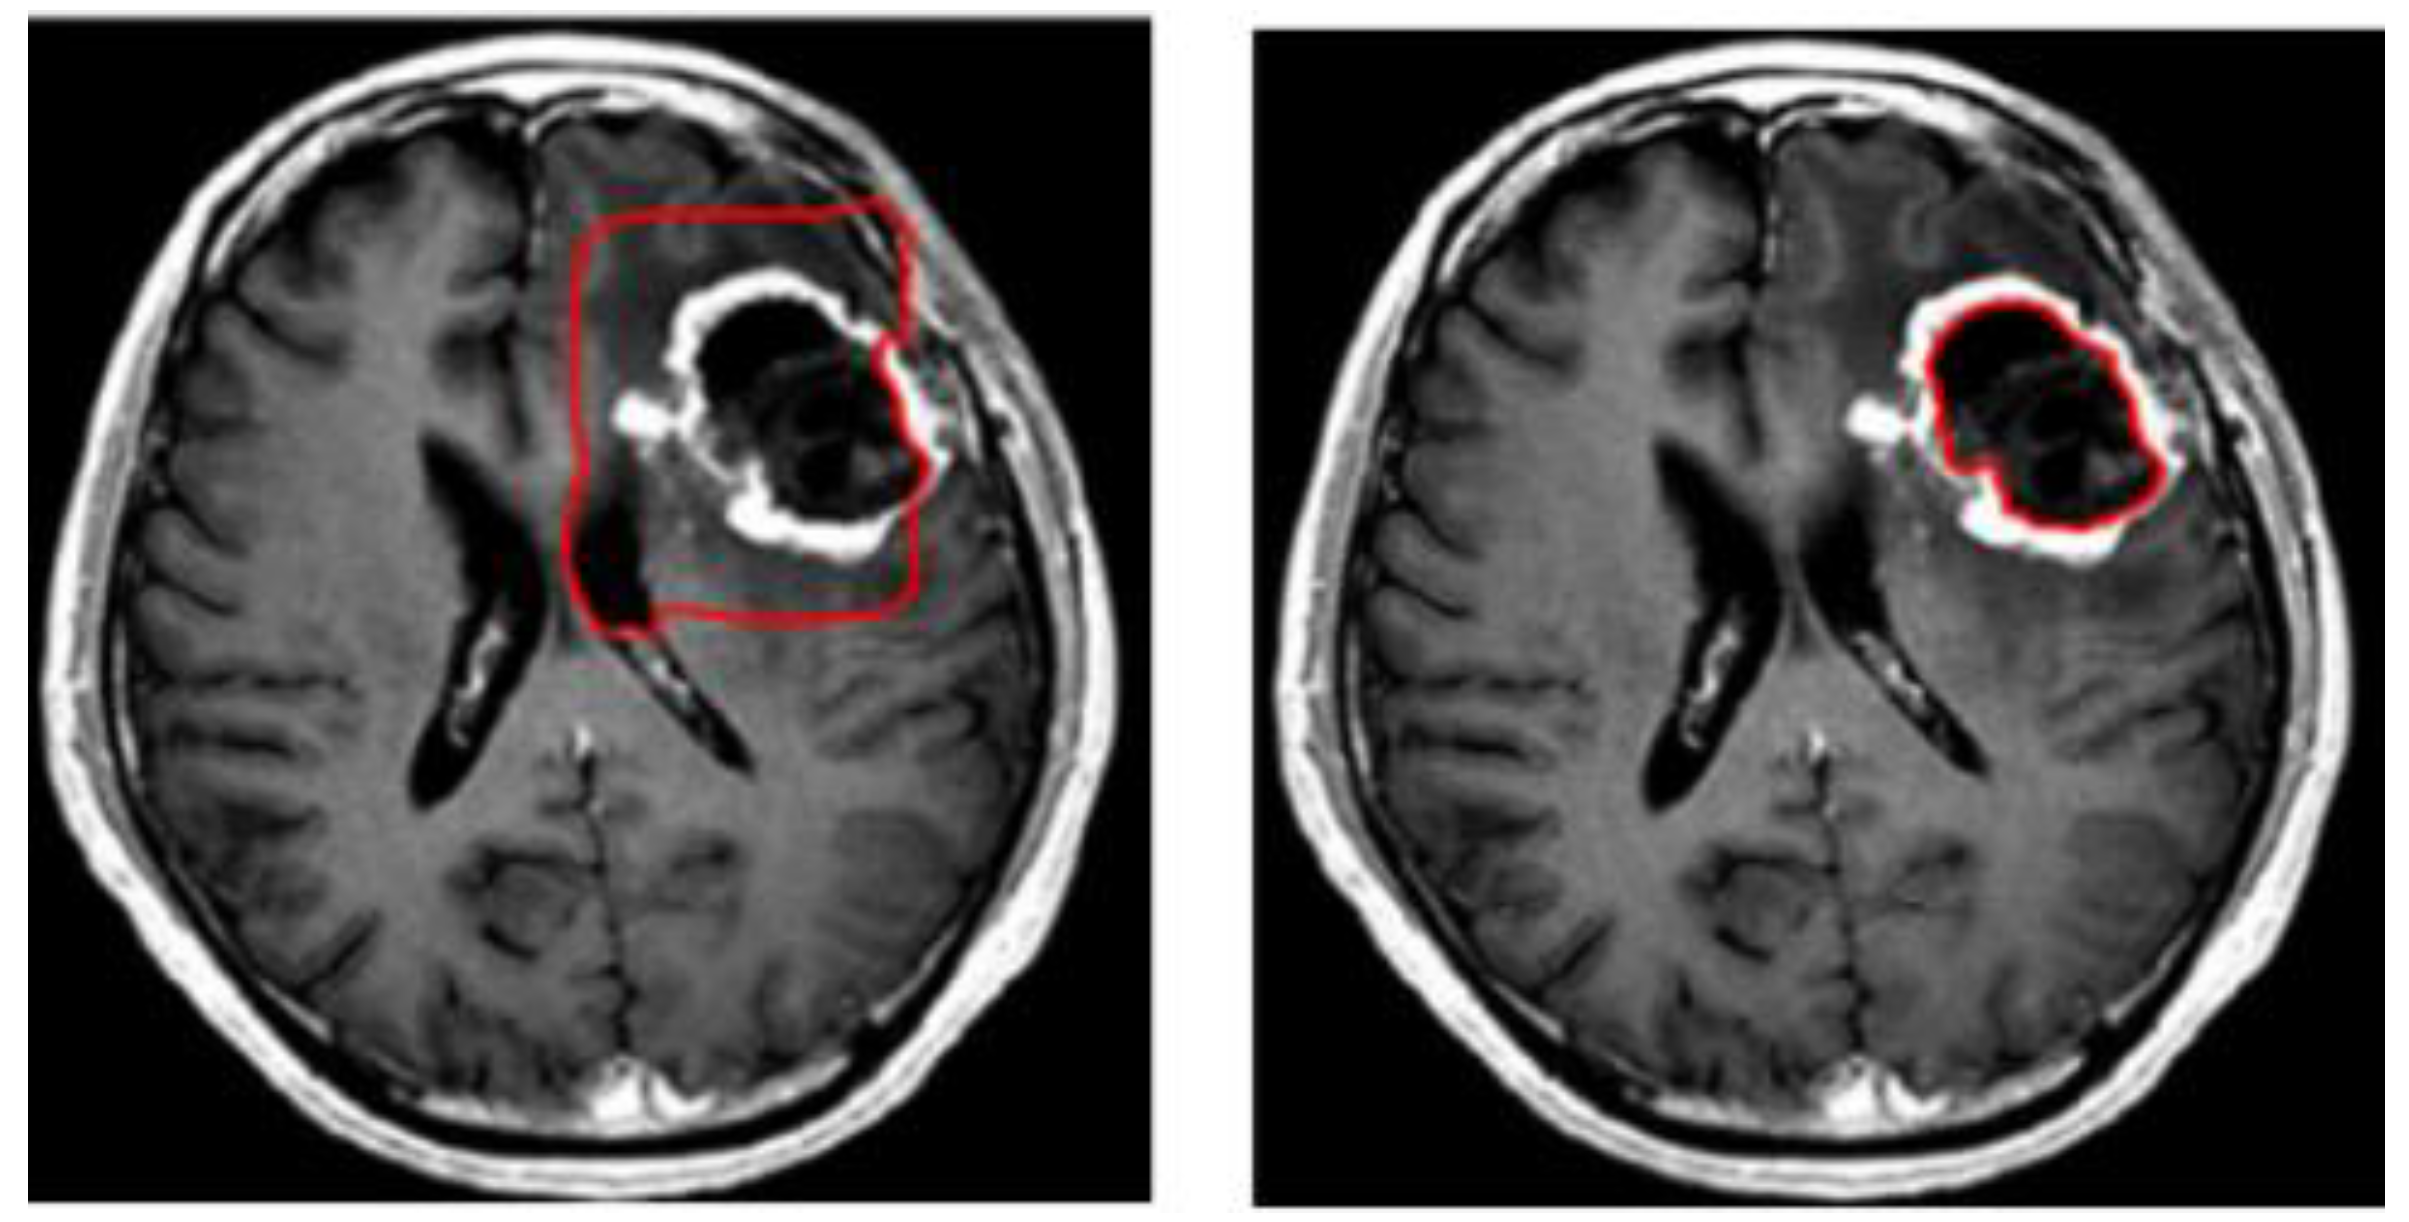

A variety of approaches have been attempted to tackle the problem of brain tumor segmentation of 3D MRI. Two methods have been proposed to deal with volumetric input. The first of these uses the idea of natural image segmentation, where the 3D volume is cut into 2D slices, and a 2D network is then trained to process each slice individually or sequentially. The second method involves cutting the volume into patches, then training a 3D network to process these patches. In the following stage, the two methods use a sliding window to test the original volume. Both methods have advantages and disadvantages [10]. Due to varying resolutions in the third dimension of the MRI dataset, 3D-MRI images are converted into 2D slices. Within the second category, level set based segmentation is broadly used. The level set method provides a direct way to estimate the geometric properties of the evolving structure. Figure 3 shows an example of brain tumor segmentation using level set after initializing the initial contour [11,12]. The advantage of using a level set representation is its ability to represent contours of complex topology and handle various topological changes, such as merging and splitting, in a natural and efficient way. To solve this optimization problem, gradient descent is used as an effective search method within the level set technique. However, the main drawbacks of gradient descent methods are their sensitivity to local optima and slow convergence.

Figure 3.

Example of brain tumor segmentation using the level set method.